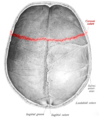

![]() Superior view of the skull. ("Coronal suture" in red.) | |

Superior view of anterior part of the skull. Coronal suture runs horizontally.